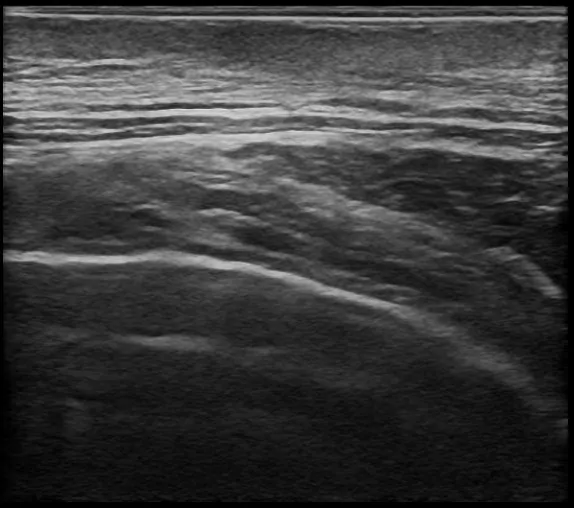

術後の経過は良好で、半年後の検診(超音波検査)では、再発の兆候は見られず、傷跡もほとんど目立たない状態まで回復されました。

術後半年後の超音波検査